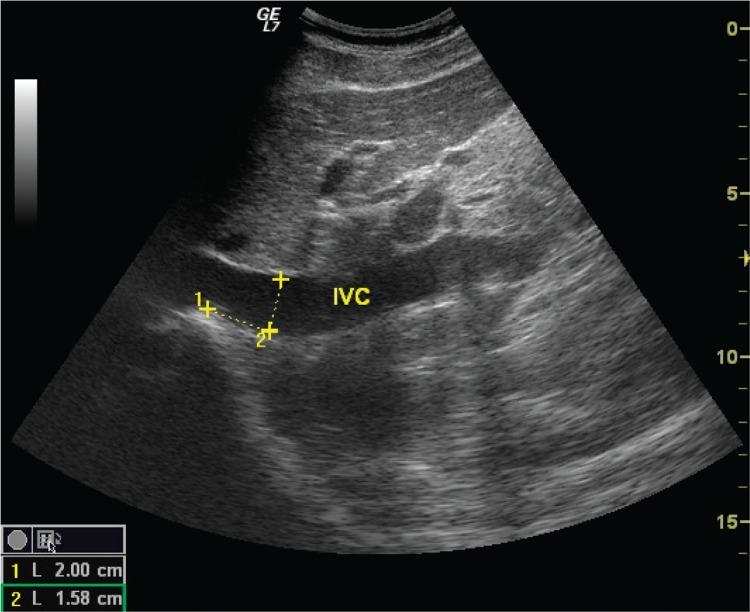

The study enrolled 45 volunteers, including 33 women, aged 22.5 ± 1.26 with a negative history of circulatory and renal diseases. The study consisted in a sonographic assessment and measurement of the inferior vena cava and aorta by placing the transducer in the anterior median line and right anterior axillary line. The value of the inferior vena cava/aorta index was obtained by calculating the ratio of the diameters of the inferior vena cava and aorta. The diameter measurements were taken by placing the ultrasound transducer in the anterior median line and right anterior axillary line. Two examiners performed the measurement three times and used convex probes of 3.5-5 MHz. Additionally, the subjects' weight, height and arterial blood pressure were taken.

Following a statistical analysis with the use of STATISTICA software, the following values of the inferior vena cava/aorta index were obtained: in the anterior median line - 1.43 ± 0.21, and in the right anterior axillary line - 1.285 ± 0.19. There was no statistically significant difference between the measurements obtained by the two examiners (p = 0.17). A strong correlation was noted between the inferior vena cava/ aorta indices calculated in both sites of transducer placement, which was irrespective of the examiners (the correlation coefficient: r = 0.61 and r = 0.71). The study indicate that the inferior vena cava/aorta index measured in the right anterior axillary line is a simple and reproducible method for determining the body fluid status; the examinations conducted in both sites may be used interchangeably. Further studies are needed to determine reference values for the inferior vena cava/aorta index measured in the right anterior axillary line.

本研究纳入了45名志愿者,其中包括33名女性,年龄为22.5±1.26岁,无循环系统和肾脏疾病史。研究包括通过将探头置于前中线和右腋前线对下腔静脉和主动脉进行超声评估和测量。下腔静脉/主动脉指数的值通过计算下腔静脉和主动脉直径的比值获得。直径测量是通过将超声探头置于前中线和右腋前线进行的。两名检查者进行了三次测量,并使用了3.5 - 5MHz的凸阵探头。此外,还测量了受试者的体重、身高和动脉血压。

使用STATISTICA软件进行统计分析后,获得了以下下腔静脉/主动脉指数的值:在前中线为1.43±0.21,在右腋前线为1.285±0.19。两名检查者获得的测量值之间无统计学显著差异(p = 0.17)。在两个探头放置部位计算的下腔静脉/主动脉指数之间存在强相关性,且与检查者无关(相关系数:r = 0.61和r = 0.71)。研究表明,在右腋前线测量的下腔静脉/主动脉指数是确定体液状态的一种简单且可重复的方法;在两个部位进行的检查可以互换使用。需要进一步研究以确定在右腋前线测量的下腔静脉/主动脉指数的参考值。